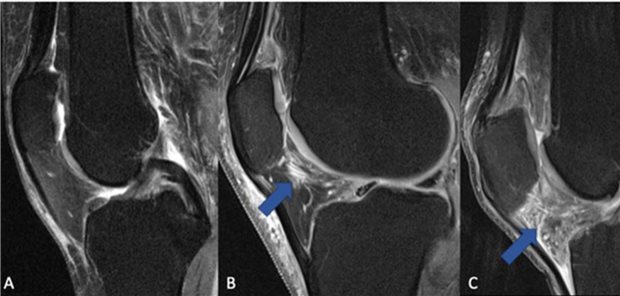

Radiologen in den USA haben Gonarthrose-Patienten mit und ohne NSAR-Therapie über vier Jahre begleitet. Sie fanden keinerlei Wirksamkeit der NSAR gegen die Entzündung und die Krankheitsprogression.